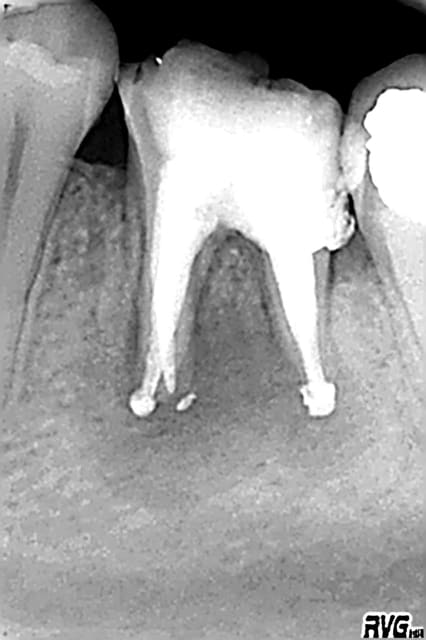

08/11/2008 à 14h03

puis des fois ça parait bien...et c'est l'extraction

radios: Mai/ aout/ octobre

tonio

10/11/2008 à 14h36

ploc écrivait:

--------------

> puis des fois ça parait bien...et c'est l'extraction

> radios: Mai/ aout/ octobre

pourquoi n'as-tu pas envisagé d'emblée l'extraction sur cette dent? l'échec était prévisible malgré la qualité de ton traitement endo, non?

tu vas me dire, facile à dire a posteriori, c'est vrai.

quand on veut sauver une dent porteuse d'une LIPOE, il y a d'autres paramètres à prendre en compte que la lésion, comme le délabrement de la dent ou encore l'accessibilité aux canaux.

Dans ton cas, force est de constater que l'accessibilité aux cas n'a pas posé de problème.

Par contre, j'aurai extrait la dent pour les raisons suivantes:

- zone interradiculaire très fragile (voire perforée)

- carie sous gingivale à mi-hauteur sur la racine D

- délabrement coronaire conséquent voire total

- racines de petite taille, probablement résorbées par la LIPOE: donc faible appui pour le futur IC et difficulté de contrôle de la longueur de l'obturation du fait de l'absence de cône apical.

ploc

10/11/2008 à 19h28

tonio écrivait:

---------------

>

> Par contre, j'aurai extrait la dent pour les raisons suivantes:

> - zone interradiculaire très fragile (voire perforée)

non,vérifié après extraction

> - carie sous gingivale à mi-hauteur sur la racine D

au 1/3

> - délabrement coronaire conséquent voire total

certes mais j'ai fait pire

> - racines de petite taille, probablement résorbées par la LIPOE: donc faible> appui pour le futur IC et difficulté de contrôle de la longueur de l'obturation

> du fait de l'absence de cône apical.

dommage,je n'ai pas eu le reflexe de prendre la dent en photo sur une compresse(vu en urgence evidemment)

la dent n'était pas fracturée,l'obturation(gutta condensée) vraiment bien

par contre c'est vrai ,racines courtes et surtout aucune recuperation osseuse

le curetage et comblement ont été plus longs que l'extract

il existait un paramètre subjectif et affectif:petit,il a partagé le mme cheval que ma fille et lui fait couler maintenant des jours heureux au pré:)

moniteur,il n'a pas trop de sous

je partais:mon rempla à qui je refile les endos difficiles qd il vient(je suis une titulaire qui aime les endos de son remplaçant et lui fait confiance:) a tenté, pr me faire plaisir,bien que sceptique(moi aussi)

hors du temps et de l'argent,on n'avait rien à perdre et le patient aurait pu gagner qqes années